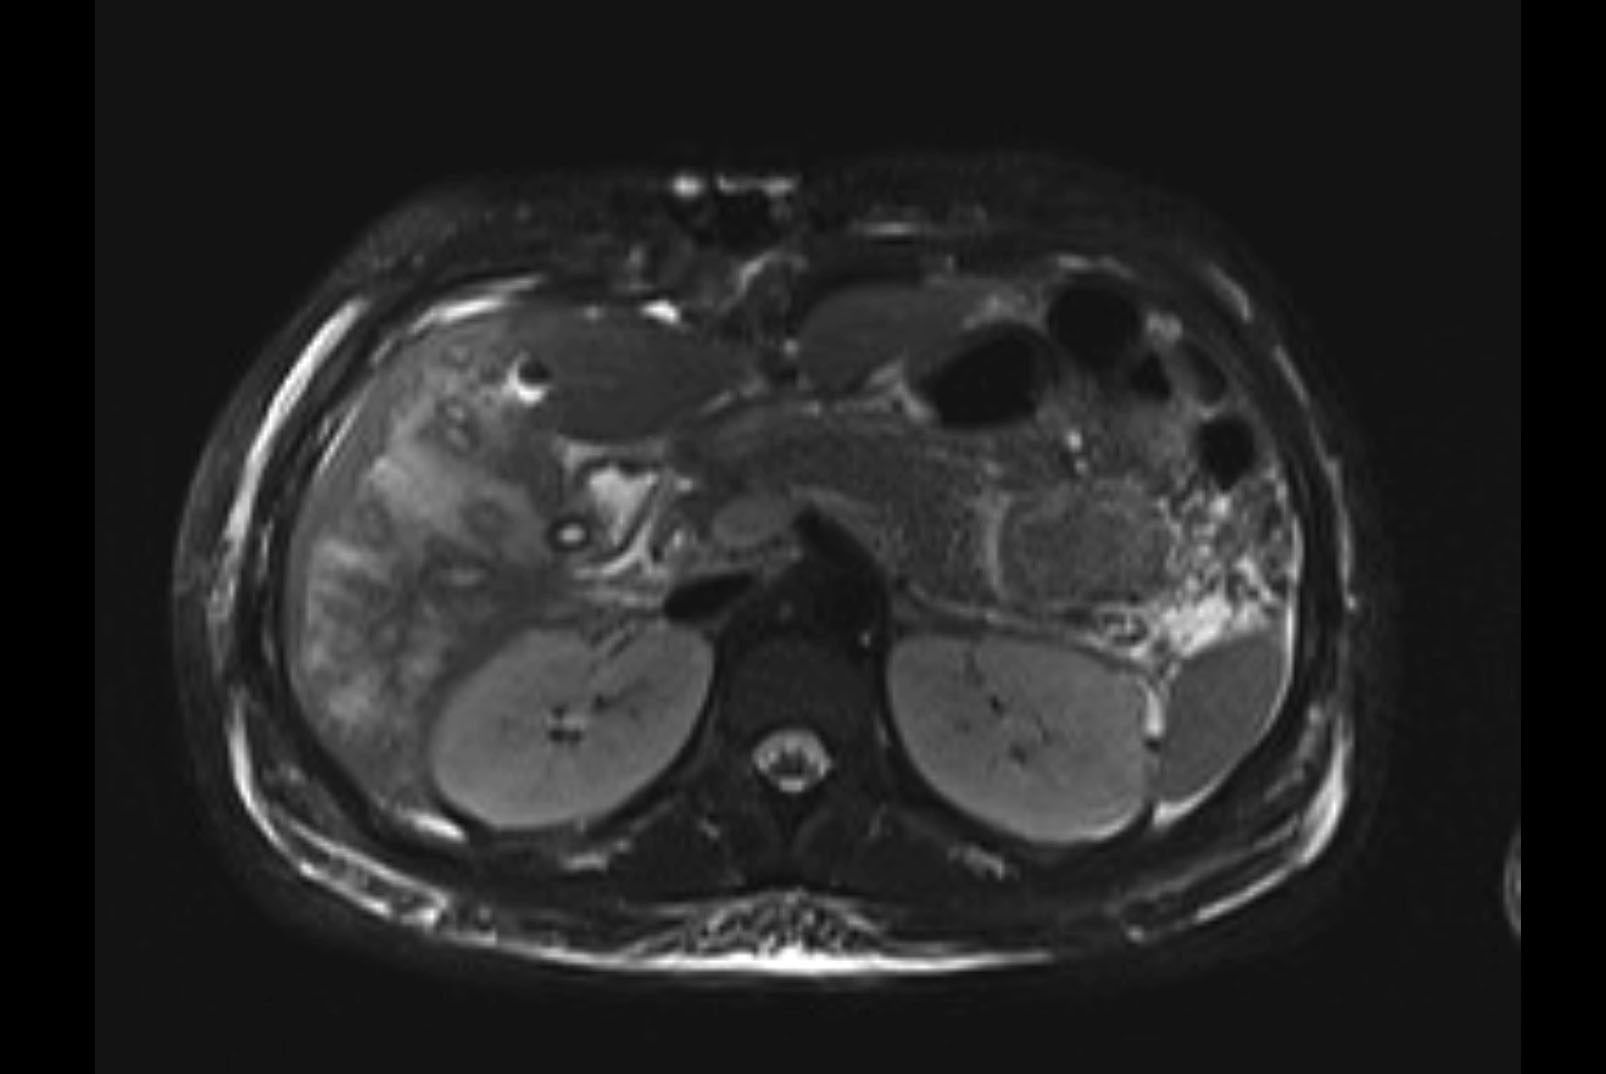

MRI T1

MRI T2

Imaging analysis

Based on initial findings, which issue(s) would you be most concerned about?